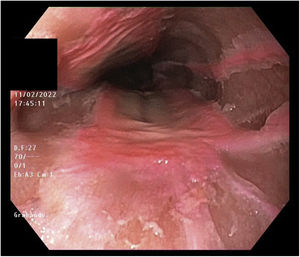

Urgent gastroscopy was performed (Fig. 1) showing an area of raised mucosa extending longitudinally for 4 cm at 30 cm from the dental arch. It did not shed and had a deep pink colouring and digitiform projections. Fibrin-covered ulcerations measuring less than 1 cm were seen around the lesion. Biopsies of the lesion were taken and the patient was discharged with double-dose proton-pump inhibitor, analgesia and liquid-shredded diet.